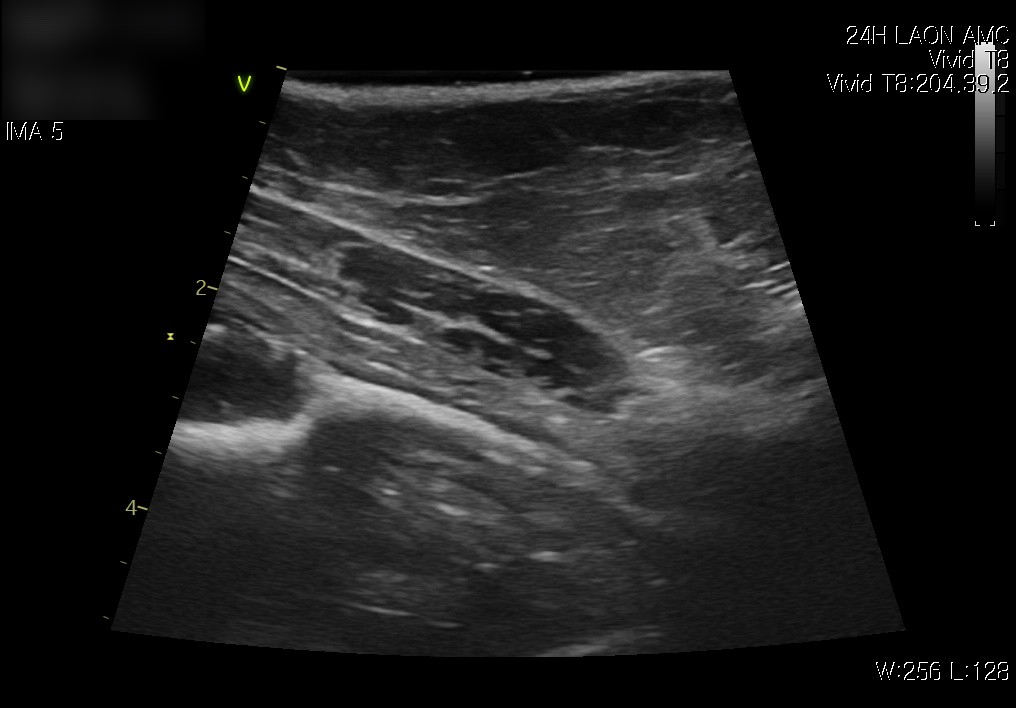

다음은 복부 초음파 검사 결과입니다.

내원 시 방광 요도 사진 / 출처: 라온동물메디컬센터

방광 초음파에서는 방광 내 염증성 변화와 소변 잔류가 관찰되었습니다.